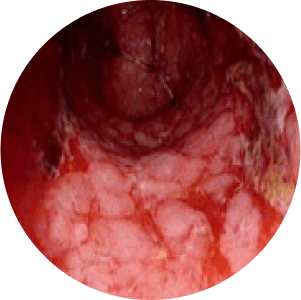

Stages of Ulcerative Colitis

stage

Noraml Mucosa

Mild Inflamation

Modearte Inflamation

Severe Inflamation